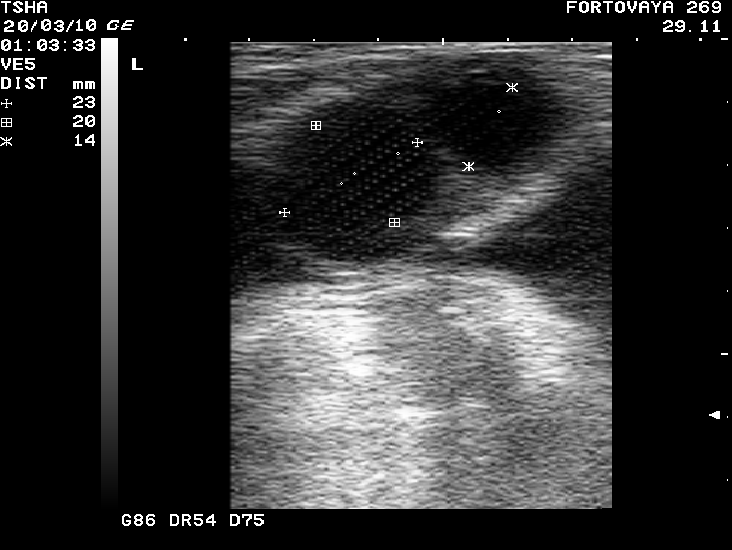

Рис. 6. Вариабельность параметров фолликуло - и кистогенеза у коровы Фартовая 269 с хронической формой кистозной болезни яичников. Сканирование яичников проводили через каждые 14 дней